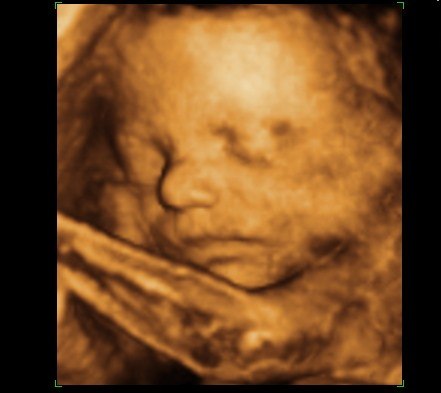

Efterfølgende er det bare blevet mere og mere omfattende for hver ny undersøgelse og scanning. I uge 10 var vi til genetisk rådgivning, da Mortens faster mangler hænder og fødder - det samme gør hendes datter. Allerede her var det lille hjerte blevet til en lille menneskefigur med boksehandsker ;o) I uge 12 var vi til NF-scanning og alt så godt ud. Igen så de efter hænder og fødder og alt var fint. Lav risiko for DS og fin baby. I uge 17 er vi til kønsscanning på en privatklinik og får at vide, at vi venter en lille pige. Fik set hende i 3D og tænk at der var sådan en fin lille en inden i min mave. Hun havde på dette tidspunkt ikke meget fedt på kroppen, så minder mest om en lille alien. Men hun er vores lille rumvæsen. I uge 19 er vi til MD-scanning og får at vide, at det er en fin lille baby, der har det godt og vokser som den skal. Hun lå med krydsede ben, så vi fik ikke bekræftet kønnet.

Jeg fik først "mave på" i uge 24, så for mig har scanningerne været guld værd - jeg kunne jo ikke se det udenpå i meget lang tid.